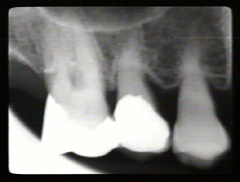

La lesión de furcación del primer molar superior presenta defectos óseos en el sitio de la furca y en mesial y distal. El segundo y primer  premolar tienen movilidad de grado I

Las radiografías periapicales muestran pérdida de hueso alveolar en aproximadamente la mitad de la longitud de la raíz. La pérdida de hueso en el área de furacación se indica por la radiolucidez aumentada en la unión de las raíces en la región cervical.

Los premolars han perdido más de la la mitad de la longitud de la raíz del hueso alveolar periodontal.  Hay defectos infraóseos en particular en el segumdo premolar en mesial y distal. El modelo semilunar que cubre la raíz del segundo premolar también indica la presencia de una defecto óseo en palatino.